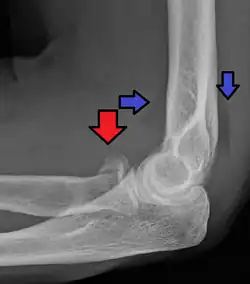

| Radial head fracture (red arrow) with posterior and anterior sail sign (blue arrows) | |

CT scan showing a radial head fracture -

Radial head fracture seen on 3D CT reconstruction